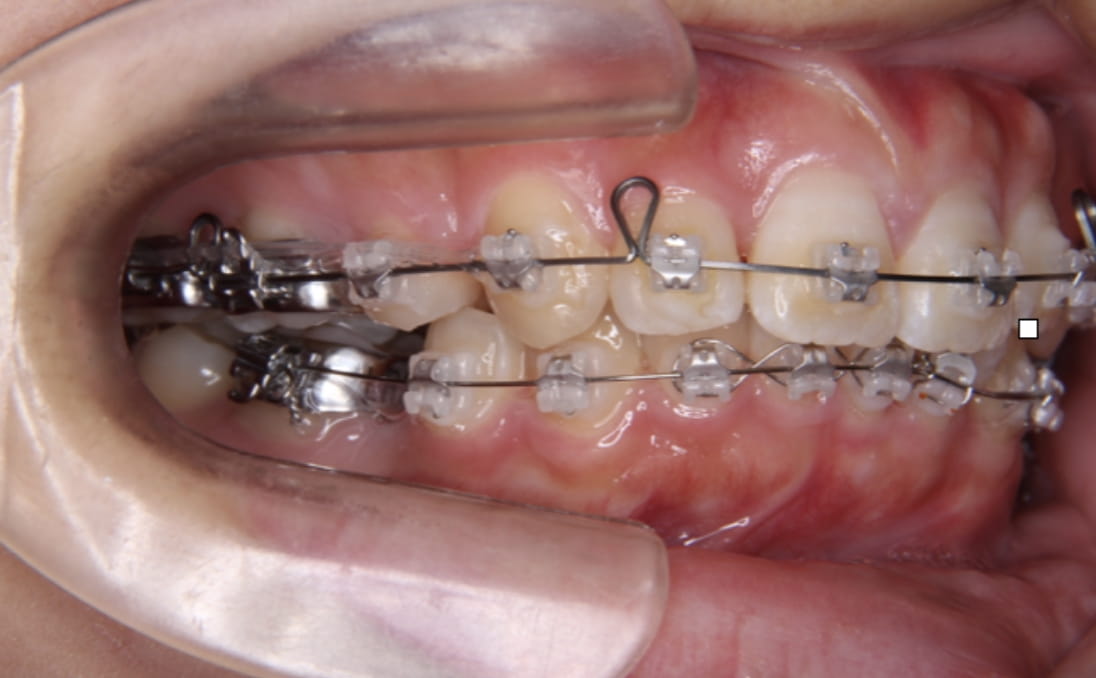

前歯を「倒す」のではなく「根元から平行に引く」技術

ここが最も重要なポイントです。前歯をただ内側に傾けるだけでは、歯が倒れて不自然な口元になります。インプラントアンカーにフックを取り付けて引っ張る、またはワイヤーにループメカニクスを組み込むことで、歯を根元から平行に後退させる歯体移動(リトラクション)が実現します。%集中できます。骨格的な突出でも、アンカーがあれば最大限まで改善できます。

前歯の「根元」と「先端」に均等に力を加えることで傾かずに平行移動します。

これが、マウスピース矯正では難しく、ワイヤー矯正が口ゴボ治療に有利な最大の理由です。

アンカー+フック牽引

アンカーにフックを掛けて前歯を平行に牽引(岡本さん・1年半後)

ループメカニクス

ワイヤーにループを組み込んで前歯を根元から平行移動(辻井さん・治療中)